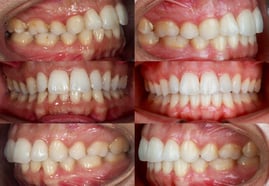

Photos Endobuccales :